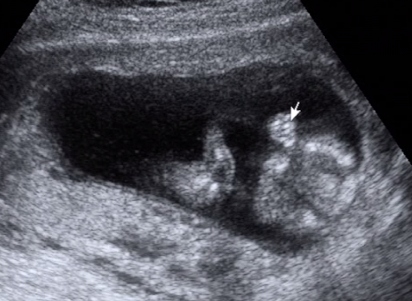

Na megérkeztünk dokitól. Mondanom sem kell hogy nagyon rendi volt. Férjem is bent volt velünk végig. Az UH-t egy nagy plazma TV-re "vetítette" ki így nagyon jól láttunk mindent.

Újra azt mondja a doki h a mérete alapján több 13 hétnél a babó...

Érdekes... Én nem bánom mondjuk ha előbb jön picit!!! :lol:

Kaptunk egy szép színes képet és a videófelvételt az UH-ról.

A doki azt mondja nem nyilatkozik de nagyon dudorodik vmi a lába között... :lol:

Szóval Mumi lehet h két tökös Bercink lesz!!!

A képeket a videóból vágtam ki...

Kép Kép

Pussz: Tigrisék